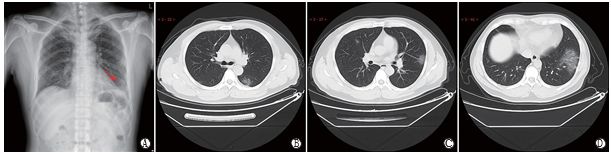

图1 典型CT/X线影像表现(例1)

男性,38岁,无明显诱因发热(39.3℃)、干咳和气短3 d。实 验室检查,WBC:6.35×109/L(正常),LYMPH%:4.1(减低), LYMPH:0.31×109/L(减低),EO:0(减低),CRP:170.91 mg/L(升高),PCT:0.45 ng/ml(升高)。A(SL:6 mm)和B(HRCT)示双肺 多发斑片状+小叶网格状小叶间隔增厚,呈典型“铺路石”征象。

图2 典型CT/X线影像表现(例2)

男性,51岁,全身酸痛、乏力1周,发热1d(39.1℃),贫血。实验室检查,WBC:9.24×109/L(正常),LYMPH%:5.1(减低), LYMPH:0.47×109/L(减低),EO:0(减低),CRP:170.91 mg/L(升高),PCT:0.45 ng/ml(升高),ESR:48 mm/h(升高)。A示左肺下叶外带斑片影;B示左肺下叶背段大片磨玻璃密度影;C示右肺上叶后段和左肺上叶下舌段胸膜下斑片状磨玻璃密度影;D示左肺下叶外基底段大片磨玻璃密度影。